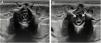

Se presenta un recién nacido a término con embarazo controlado. Al nacimiento presenta un mechón de pelo (fig. 1) de 3×2cm a nivel lumbar, palpándose fondo óseo sin otras alteraciones, con exploración neurológica acorde a su edad. Se solicita ecografía lumbosacra (fig. 2) objetivándose duplicación medular, compatible con diastematomielia dorsolumbar. Se amplía el estudio con RM cerebral y medular (fig. 3) confirmándose el diagnóstico inicial. Se realiza seguimiento por Neurocirugía con programación de la intervención a los 6 meses.

Dos cortes axiales ecográficos consecutivos en la médula lumbar (A y B) a nivel de los hilios renales, en los que apreciamos la existencias de dos hemimédulas (flechas en B). Las imágenes centrales, mediales en cada una de las hemimédulas, puntiformes e hiperecogénicas, corresponden a los respectivos epéndimos (flechas en A). No se aprecia defecto óseo asociado en los elementos lumbares posteriores (flechas negras).